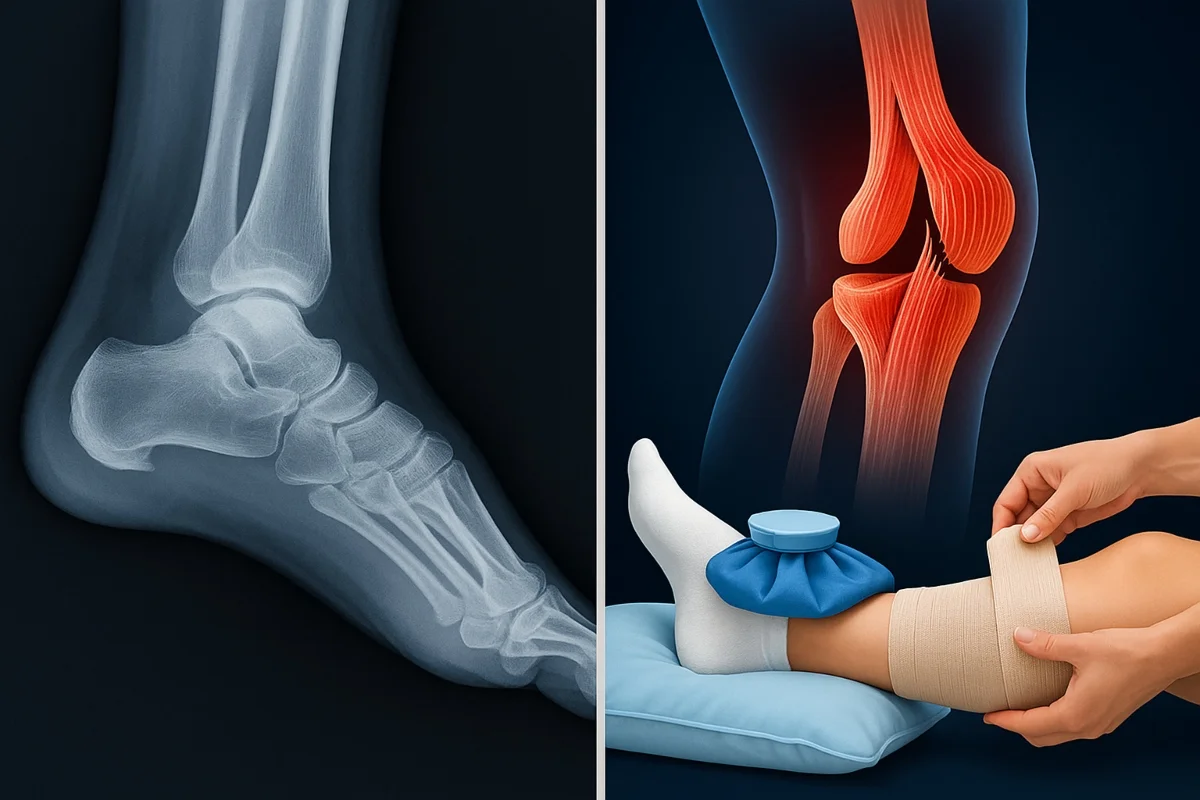

Dr Ankit Jose explains that fracture vs ligament rupture cases may share swelling and sudden pain, yet they behave differently from the very first moment. A fracture creates sharp pain that rises with every small touch or gentle move, and the person often cannot place weight on the limb. A visible deformity may appear when the break shifts bone alignment, and this makes quick imaging crucial.

Doctors depend on X-rays for clear fracture diagnosis and treatment, and this helps them plan the next step with confidence. A ligament rupture causes pain around the soft tissue near the joint, and movement may still be possible in many cases. Doctors check joint stability first and then use an MRI when they need to grade the tear before planning ligament rupture recovery tips.